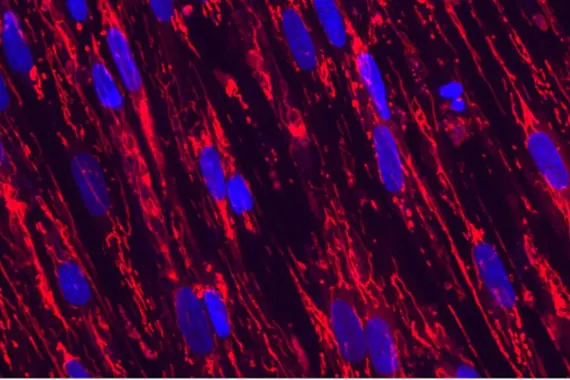

Heart muscle cells.

Cardiovascular and metabolic diseases

Our Cardiovascular & Metabolic Diseases team works to better understand the root causes of cardiovascular and metabolic diseases, and discover and develop therapies against relevant targets.